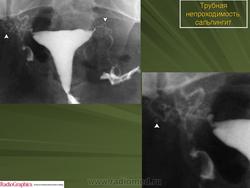

Гидросальпингс.